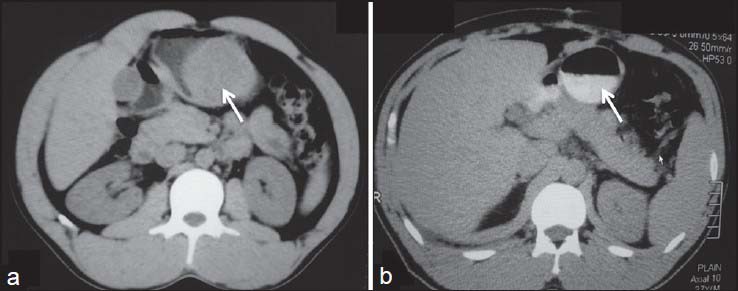

On imaging, GISTs may be submucosal, intramural or subserosal. Findings on barium studies are often subtle than seen on computed tomography (CT) as majority of them are exophytic in nature. On CT, small GISTs are usually well-defined, solid mass showing homogenous enhancement [Figure 9]. Calcifications may occasionally be present. Large tumors show areas of hemorrhage, cystic/necrotic areas and heterogeneous enhancement. Neovascularity may be seen within the tumor after contrast administration [Figure 10]. Thrombosis of mesenteric vessels is uncommon. Rarely, these tumors may be entirely cystic [Figure 11]. Cavitory nature with air and contrast within the mass is suggestive of mucosal ulceration with fistulous communication of necrotic cavity with the bowel lumen [Figure 12].[3,4] Collection of air in the nondependent aspect of larger cavitating tumors with necrosis is known as the “Toricelli-Bernouilli” crescentic necrosis sign [Figure 13].[5] Uncommon features with GIST are presence of ascites, lymphadenopathy, intestinal obstruction and metastases in lungs [Figure 14]. Crucial role lies in differentiation of benign versus malignant GISTs. Features associated with poor prognosis include distal location, size and high mitotic activity with the exception of esophageal GISTs.[6] Benign lesions are usually <2>5 cm.[7] Smaller tumors should be classified as at lower risk for malignancy rather than as benign. Tumor necrosis, cystic change, nuclear atypia, tumor vascularity, and degree of staining for CD117 are unreliable predictors of malignancy.[8] Metastases are most common in the liver, mesentery, and peritoneum [Figure 15].[9,10] Calcification is usually seen in metastases after specific chemotherapy.

Complete surgical excision is the treatment of choice. Unlike carcinomas, resection of GISTs does not require wide bowel excision or lymphadenectomy as these tumors usually do not show lymph node metastases.[8] However, despite apparently complete resection with clear margins, the recurrence rate is high. Chemotherapy with imatinib mesylate, a tyrosine kinase inhibitor has been found to be highly effective in treatment of metastatic GIST. Imatinib mesylate has revolutionized the management of GIST. Now it is often used as the first-line treatment for unresectable, metastatic, or recurrent GIST. Although complete responses are rare, a large majority of patients with metastatic or inoperable GIST have either a partial response or disease stabilization after starting imatinib. Median survival rates have gone from <2>5 years since the advent of imatinib therapy.[11] Role of imaging also lies in response evaluation of patients treated with imatinib. Response to imatinib is characterized by decreased enhancement, resolution of the enhancing tumor nodules and a decrease in tumor neovascularity [Figures [Figures1616--20].20]. These changes are usually seen within 1-month of initiation of chemotherapy. Initially, tumors may enlarge during treatment due to intratumoral hemorrhage and myxoid degeneration. Enlargement with an overall decrease in tumor enhancement suggests a favorable response. Presence of new enhancing nodules within the tumor is consistent with recurrence.[12]

| Figure 17:Metastatic gastrointestinal stromal tumors posttreatment — (a) axial noncontrast computed tomography scan showing multiple metastasis in liver (b) Posttreatment calcification is seen within the metastatic lesions with reduction in size

| Figure 17:Metastatic gastrointestinal stromal tumors posttreatment — (a) axial noncontrast computed tomography scan showing multiple metastasis in liver (b) Posttreatment calcification is seen within the metastatic lesions with reduction in size